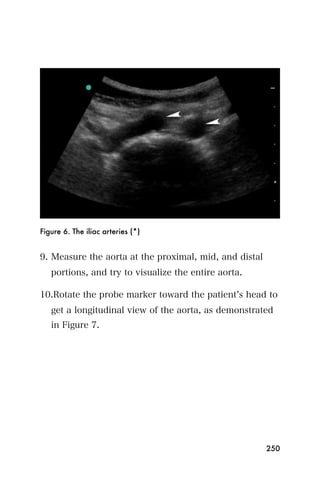

Recommended Reading

1. Andrews EJ, Fleischer AC. Sonography for deep venous

thrombosis: current and future applications. Ultrasound Q.

2005;21(4):213-225.